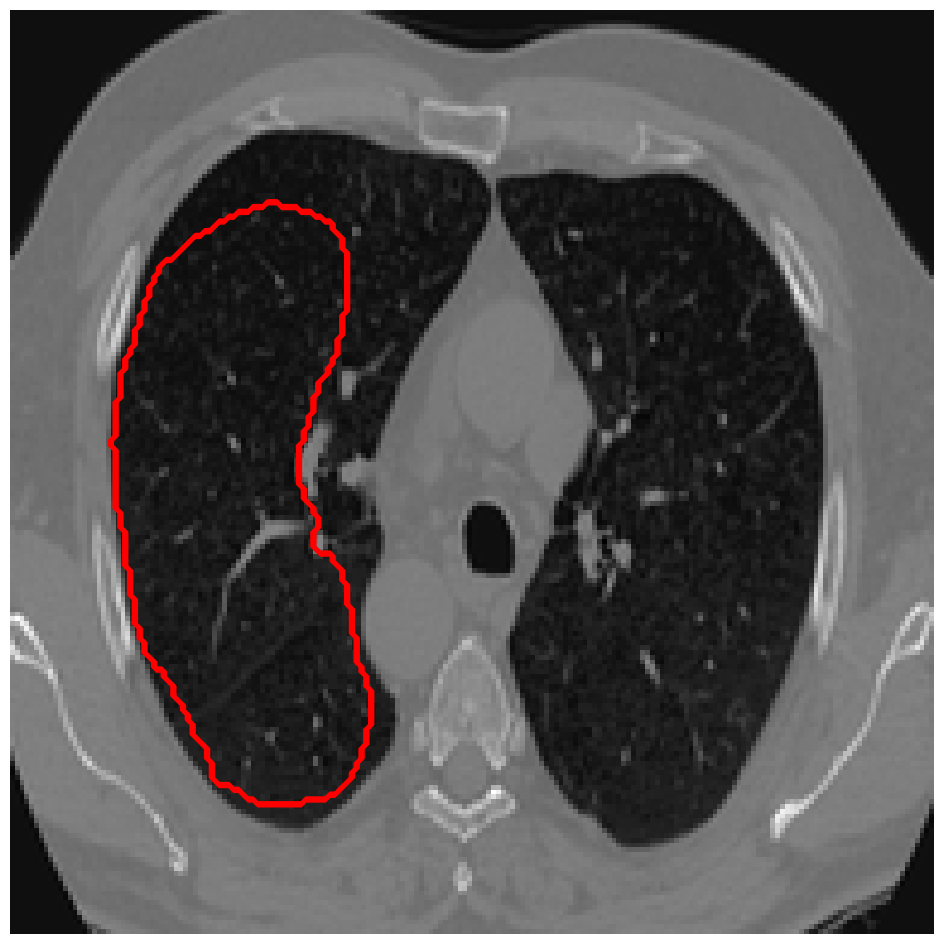

Figure 3: A sample result on the Lung data. We display the input image with the user input \mathcal{M}, the ground truth (GT) and results from the four methods. Moreover, we show comparisons with the model (4) solved in a variational framework with both Total Variation (TV) and Euler Elastica as explicit regularisation, as well as a comparison with the model solved in a Deep Image Prior framework.

In Figures 3 and 4 we show two select images from the test set for the Lung images to qualitatively show some results. To begin, we show some results of the model (1) solved with a Total Variation (TV) [21] regulariser, and with a Euler Elastica [22] regulariser. In addition, we show a result with the model (1) in a typical Deep Image Prior framework (i.e. training a network specifically for that image without the explicit regularisation in the loss function, employing early stopping). We see that the result from M4 is an improvement over the TV and Elastica models, whereas results from the DIP example is comparable. However, the DIP example requires a new network trained specifically for the new image, whereas our result is acquired after training. In addition to the explicit regularisation comparison, we also display the results from the four methods (all of which are trained previously on 222 images and used for prediction). Moreover some quantitative results are shown in table 1, which shows the mean DICE score and standard deviation on the 16 images in the test set.